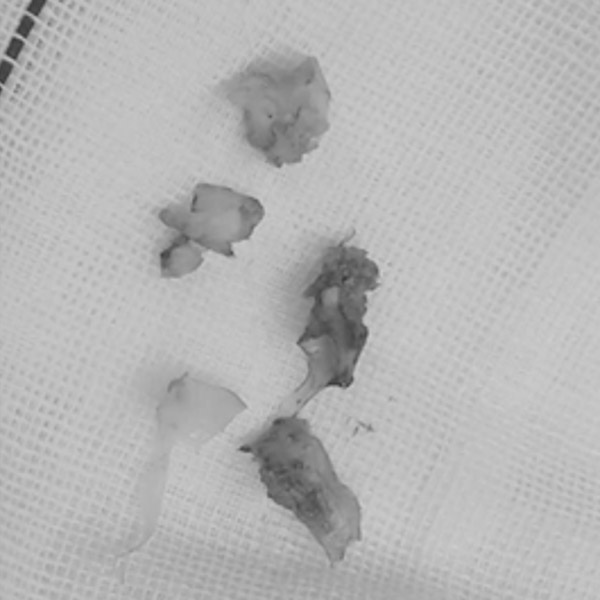

經(jīng)過充分的準(zhǔn)備,多學(xué)科共同協(xié)作,為徐阿婆行頸動(dòng)脈內(nèi)膜剝脫術(shù),最終順利切除一塊長(zhǎng)約2cm的斑塊。術(shù)后復(fù)查頸動(dòng)脈CTA,顯示右側(cè)頸內(nèi)動(dòng)脈重度狹窄恢復(fù)正常。